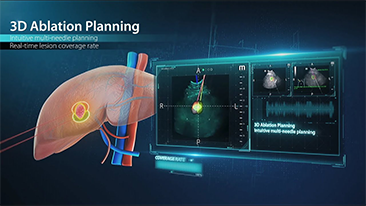

Quanto chiaramente puoi visualizzare il fegato?

Per le lesioni focali epatiche, come l'emangioma o il tumore al fegato, l'imaging di contrasto a ultrasuoni svolge un ruolo importante. La tecnologia di imaging di contrasto Ultra-wideband non-linear UWN+ consente di ottenere una migliore penetrazione, un rapporto contrasto-tessuto pi├╣ elevato con un indice meccanico pi├╣ basso e un'osservazione del tempo di perfusione pi├╣ lunga.